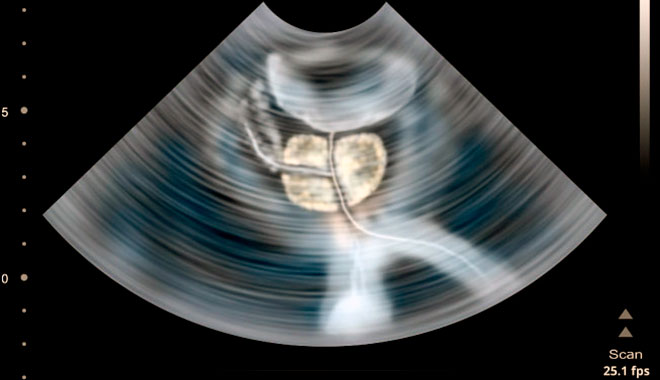

Если результаты анализов неудовлетворительные: повышенное СОЭ (скорость оседания эритроцитов), высокое содержание лейкоцитов, врач может направить пациента на УЗИ исследование и томографию.